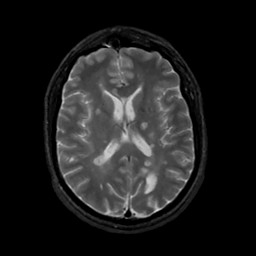

MR Study #10, April 28, 1991 -- Slice #29

[Home][Help][Clinical][Tour 1][Tour 2] Slice 29